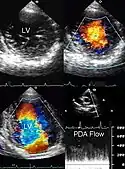

Flujo sanguíneo |